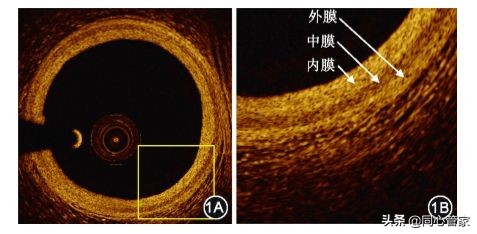

正常冠状动脉血管壁的特征是典型的3层结构,由内膜、中膜和外膜组成(如图所示)[3],内膜信号(密度)高,无病变时非常薄。但当出现病变时,OCT图像上的斑块类型可分为3类,即纤维斑块、钙化斑块和脂质斑块。

▲OTC检查血管正常图(1B是1A的放大图)[3]